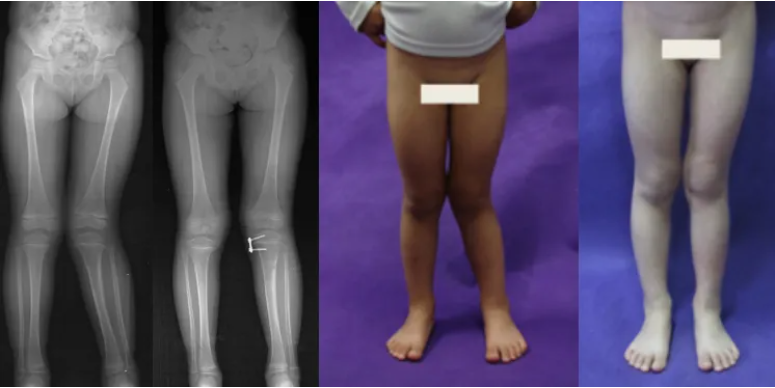

膝外翻畸形

采用半骨骺阻滯術(shù),畸形矯正后去除鋼板,恢復(fù)生長(zhǎng),手術(shù)微創(chuàng),易行。